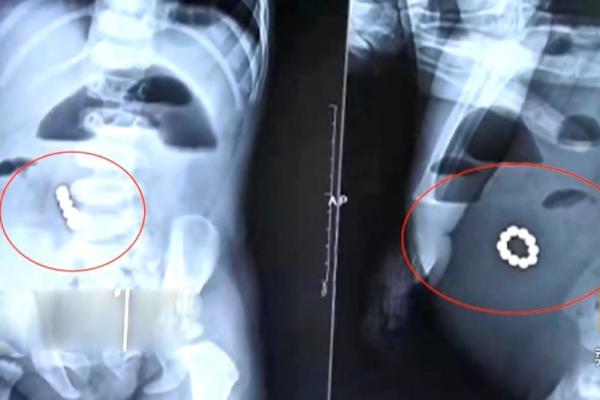

醫生動手術取出男嬰腹中的磁力珠。圖:互聯網

醫生張正茂表示:「他如果是吃下一個磁力珠,這個磁力珠會排泄出來;他如果吃下多個,牠們會相互吸引,就排不下來了。吸到一起的後果,就是腸穿孔,而且這種穿孔是多處的,所以手術的時候,需要仔細地探查。」

手術開始後,醫生們通過腸道穿孔的位置,迅速找到了4顆磁力珠;然後,他們順著男嬰的胃和腸子一寸、一寸地探查,又找到了6顆磁力珠。當這10顆磁力珠被放置在一起時,它們迅速圍攏起來,形成了手鏈的模樣。

男嬰的家長事後表示,這串磁力珠,原本是他們買給10歲的大兒子玩的,沒想到卻被1歲多的小兒子誤吞進肚子裡,也使得一般情況下1個小時就能完成的手術,足足做了2個多小時才結束。現在,男嬰的病情已明顯好轉,正在康復中。